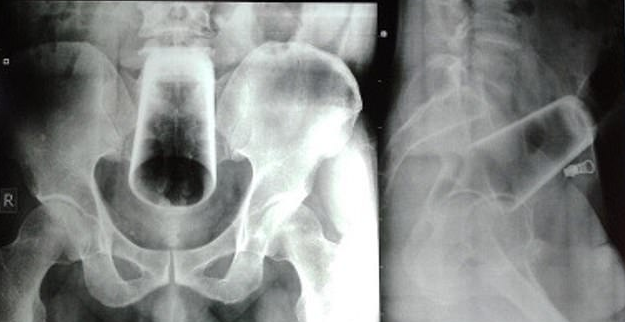

Bei der Untersuchung waren seine Stimmung und sein Verhaltensmuster "normal", und er hatte keine psychiatrischen Erkrankungen. Röntgenaufnahmen zeigten ein Wasserglas in umgekehrter Position im oberen Rektum und im Dickdarm. Die Ärzte lehnten eine Sigmoidoskopie ab - ein Verfahren, das es den Ärzten ermöglicht, mit Hilfe eines flexiblen Schlauches mit Licht in das Innere des Dickdarms zu schauen -, weil sie befürchteten, dass das Glas "beim Entfernen" zerbrechen würde.